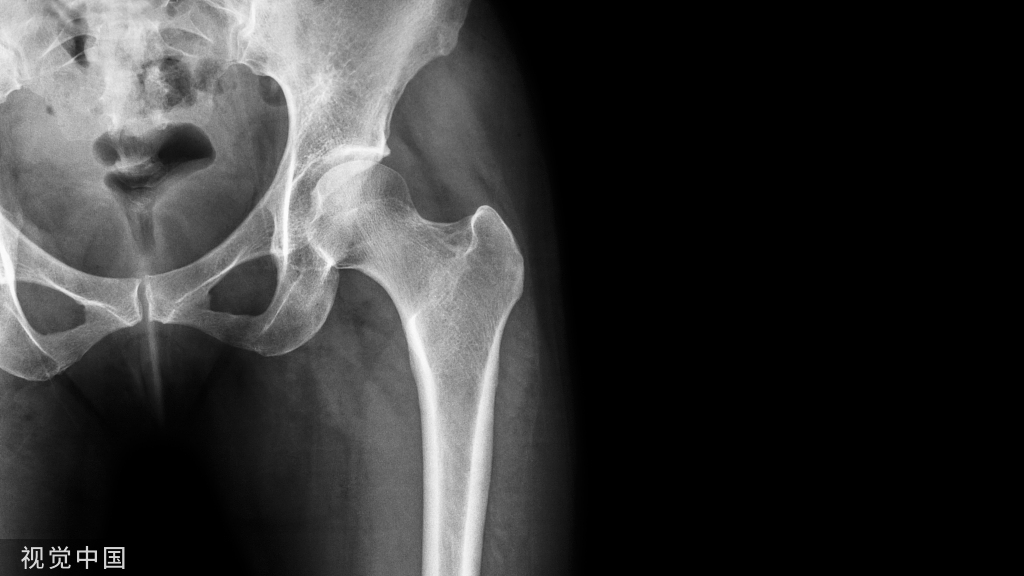

英国儿童肌肉骨骼感染管理共识指南

本研究的目的是确定英国肌肉骨骼感染(包括化脓性关节炎、骨髓炎、脓肌炎、腱鞘炎、筋膜炎和椎间盘炎)儿童(0至15岁)调查和管理的共识最佳实践方法。这一共识可用于确保英国医院和其他拥有类似医疗保健系统的医院为儿童提供一致、安全的护理。